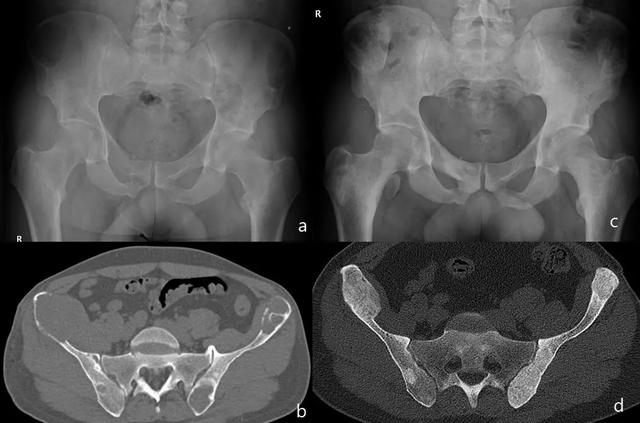

放射学特征是单个或多个溶解性病变,具有良好的边缘,可以扩张和皮质变薄。它的破坏性方面和多灶性分布是转移的一个方面。缺乏已知的原发性肿瘤,存在软骨钙质沉着,高甲状旁腺激素和钙血清水平有助于诊断(图13-15)。

图13:棕色瘤。正位骨盆和轴向两侧髋关节X线片:髂嵴和股骨上的骨溶解性病变(红色箭头)(a,b和c)。在CT上,右髂嵴病变有皮质溶解和相关的软组织肿块(绿色箭头),以及其他明确边缘的病变,一些可见硬化边缘(d)。我们发现右侧髋部的软骨钙质沉着症(黄色箭头)(e)。

图15:棕色瘤。去除功能亢进的甲状旁腺腺瘤,(a和b)之前和之后(c和d)的图像,患上骨饥饿综合症再溶解后的溶骨性病变,这需要静脉注射钙。(骨饥饿综合征hungry bone syndrome:是骨组织成骨活性增高或正常而骨吸收被强烈抑制的一种病理状态,以骨脱钙、骨变形、病理性骨折、高血钙、肾结石等一系列病理活动过程为主要表现的疾病的总和。临床少见,主要分为原发性、继发性、三发性三大类。原发性骨饥饿综合征可根据血钙增多、血磷降低、血碱性磷酸酶升高,临床表现、B超、Cr、X线等术前诊断并不十分困难,但由于该病临床少见,国内积累病例不过1000余例,临床上往往由于症状分散,且多数按"风湿"、"骨病"等治疗,当出现了全身骨痛、肌无力、反复病理性骨折及肾结石时才被确诊,所以病程较长,多属中晚期。)